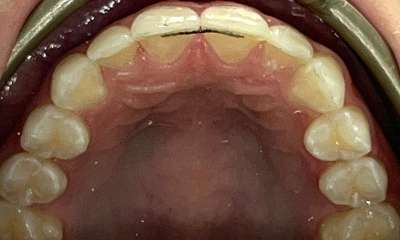

What a smile! It’s so nice to see Invisalign in progress and the confidence it brings, even in the process. In this case it took nine months of Invisalign clear aligners for Dr Gourlay to correct this patient’s crowding. The patient and family are thrilled with the result.